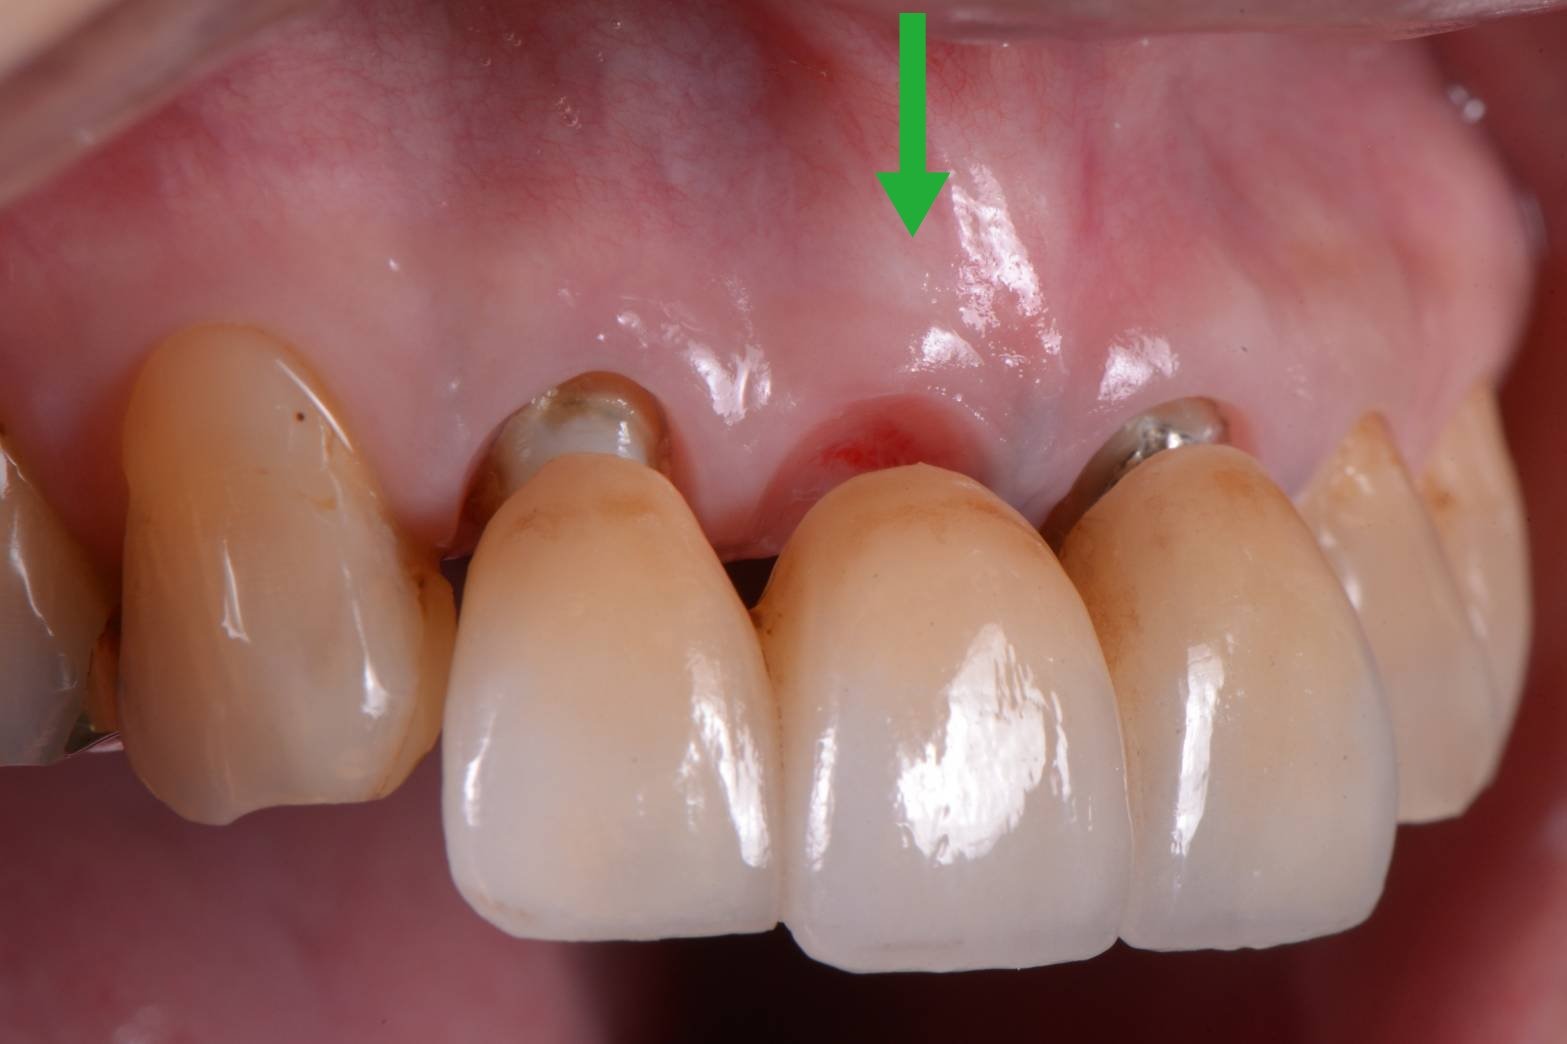

この緑の矢印の歯でした。

このように歯があるように見せるためのセラミックの形態をオペイドポンティックと呼びます。

オベイドとは卵円型という意味で、歯肉の形態もそのような形になっています。

歯肉にセラミックを押し込むため、異物反応が出ないジルコニアやセラミックが用いられてます。これをチタン以外の金属でやると腫れて膿んできます(>_<)